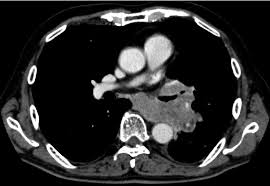

A ct scan test can also be used to look for the spread of lung cancer in the adrenal. Once a nodule is found, a workup is done to see if it is cancer. It is used to look for early signs of lung cancer. Ct scans of the chest are used to find lung nodules or other chest pathology. Awareness of the possible causes of overlooking a pulmonary lesion can give radiologists a chance to reduce the occurrence of this eventuality. This can provide definitive evidence of the disease. If you are a smoker, it is highly recommended to have a ct scan every 3 months. It gives detailed information about your cancer. It's equal to about half the radiation you're exposed to naturally from the environment in a year. Another doctor might be able to recommend other testing options. Your doctor might use imaging tests to look for unusual growths inside your body that might be cancer. Computed tomography (ct) scans detect tumors, but do not determine whether they are malignant or not. The doctor will then order additional testing to rule out or confirm a cancer diagnosis.

But the test is not helpful for light smokers or people who quit smoking more than 15 years ago. Early detection of lung cancer means more treatment options an excellent tool for people at high risk for lung cancer the scan is quick, painless and noninvasive ct imaging is detailed and accurate and can reveal the smallest of abnormalities The scan looks at your lungs and other parts of your chest. Ct is highly accurate for lung cancer detection. Nevertheless, lung cancer can also be overlooked on computed tomography (ct) scans, regardless of the context, either if a clinical or radiologic suspect exists or for other reasons. A ct scan test can also be used to look for the spread of lung cancer in the adrenal. If you are at higher risk, talk to your doctor about getting screened. The smallest recesses of the chest can be clearly seen. It can also show the size, shape, and position of any lung tumors and can help find enlarged lymph nodes that might contain cancer that has spread. Therefore, ct scans can lead to a false negative this can negatively impact your ability to get any treatment at all Ct scans of the chest are used to find lung nodules or other chest pathology. Alternatively, you should take lung ct scans if you are concerned or if you show any symptoms. It can also look at your liver and adrenal glands.

New Program To Detect Early Lung Cancer In Current And Former Smokers Newsroom Weill Cornell Medicine from news.weill.cornell.edu Therefore, ct scans can lead to a false negative this can negatively impact your ability to get any treatment at all Computed tomography (ct) scans detect tumors, but do not determine whether they are malignant or not. A ct scan test can also be used to look for the spread of lung cancer in the adrenal. Ct is highly accurate for lung cancer detection. The scan looks at your lungs and other parts of your chest. It is used to look for early signs of lung cancer. A ct scan can detect potential cancer in a lung. It gives detailed information about your cancer.

The scan looks at your lungs and other parts of your chest. Lung cancer screening carries several risks, such as: It can also show whether the cancer has spread outside the lung. It is used to look for early signs of lung cancer. 234 views answered >2 years ago A computer then combines these images into a detailed picture of your lungs. A ct scan can detect potential cancer in a lung. Alternatively, you should take lung ct scans if you are concerned or if you show any symptoms. Are you preparing to have this procedure soon? If the test finds cancer, treatment can start early. If cancer is diagnosed, other tests will be performed to stage and grade the tumor so that the appropriate treatment can be delivered. If you're still concerned about radiation from a ct scan, you can always get a second opinion. Lung biopsy, involving the extraction of suspicious tissues by needle or other methods, is ordered if a ct scan suggests cancer.